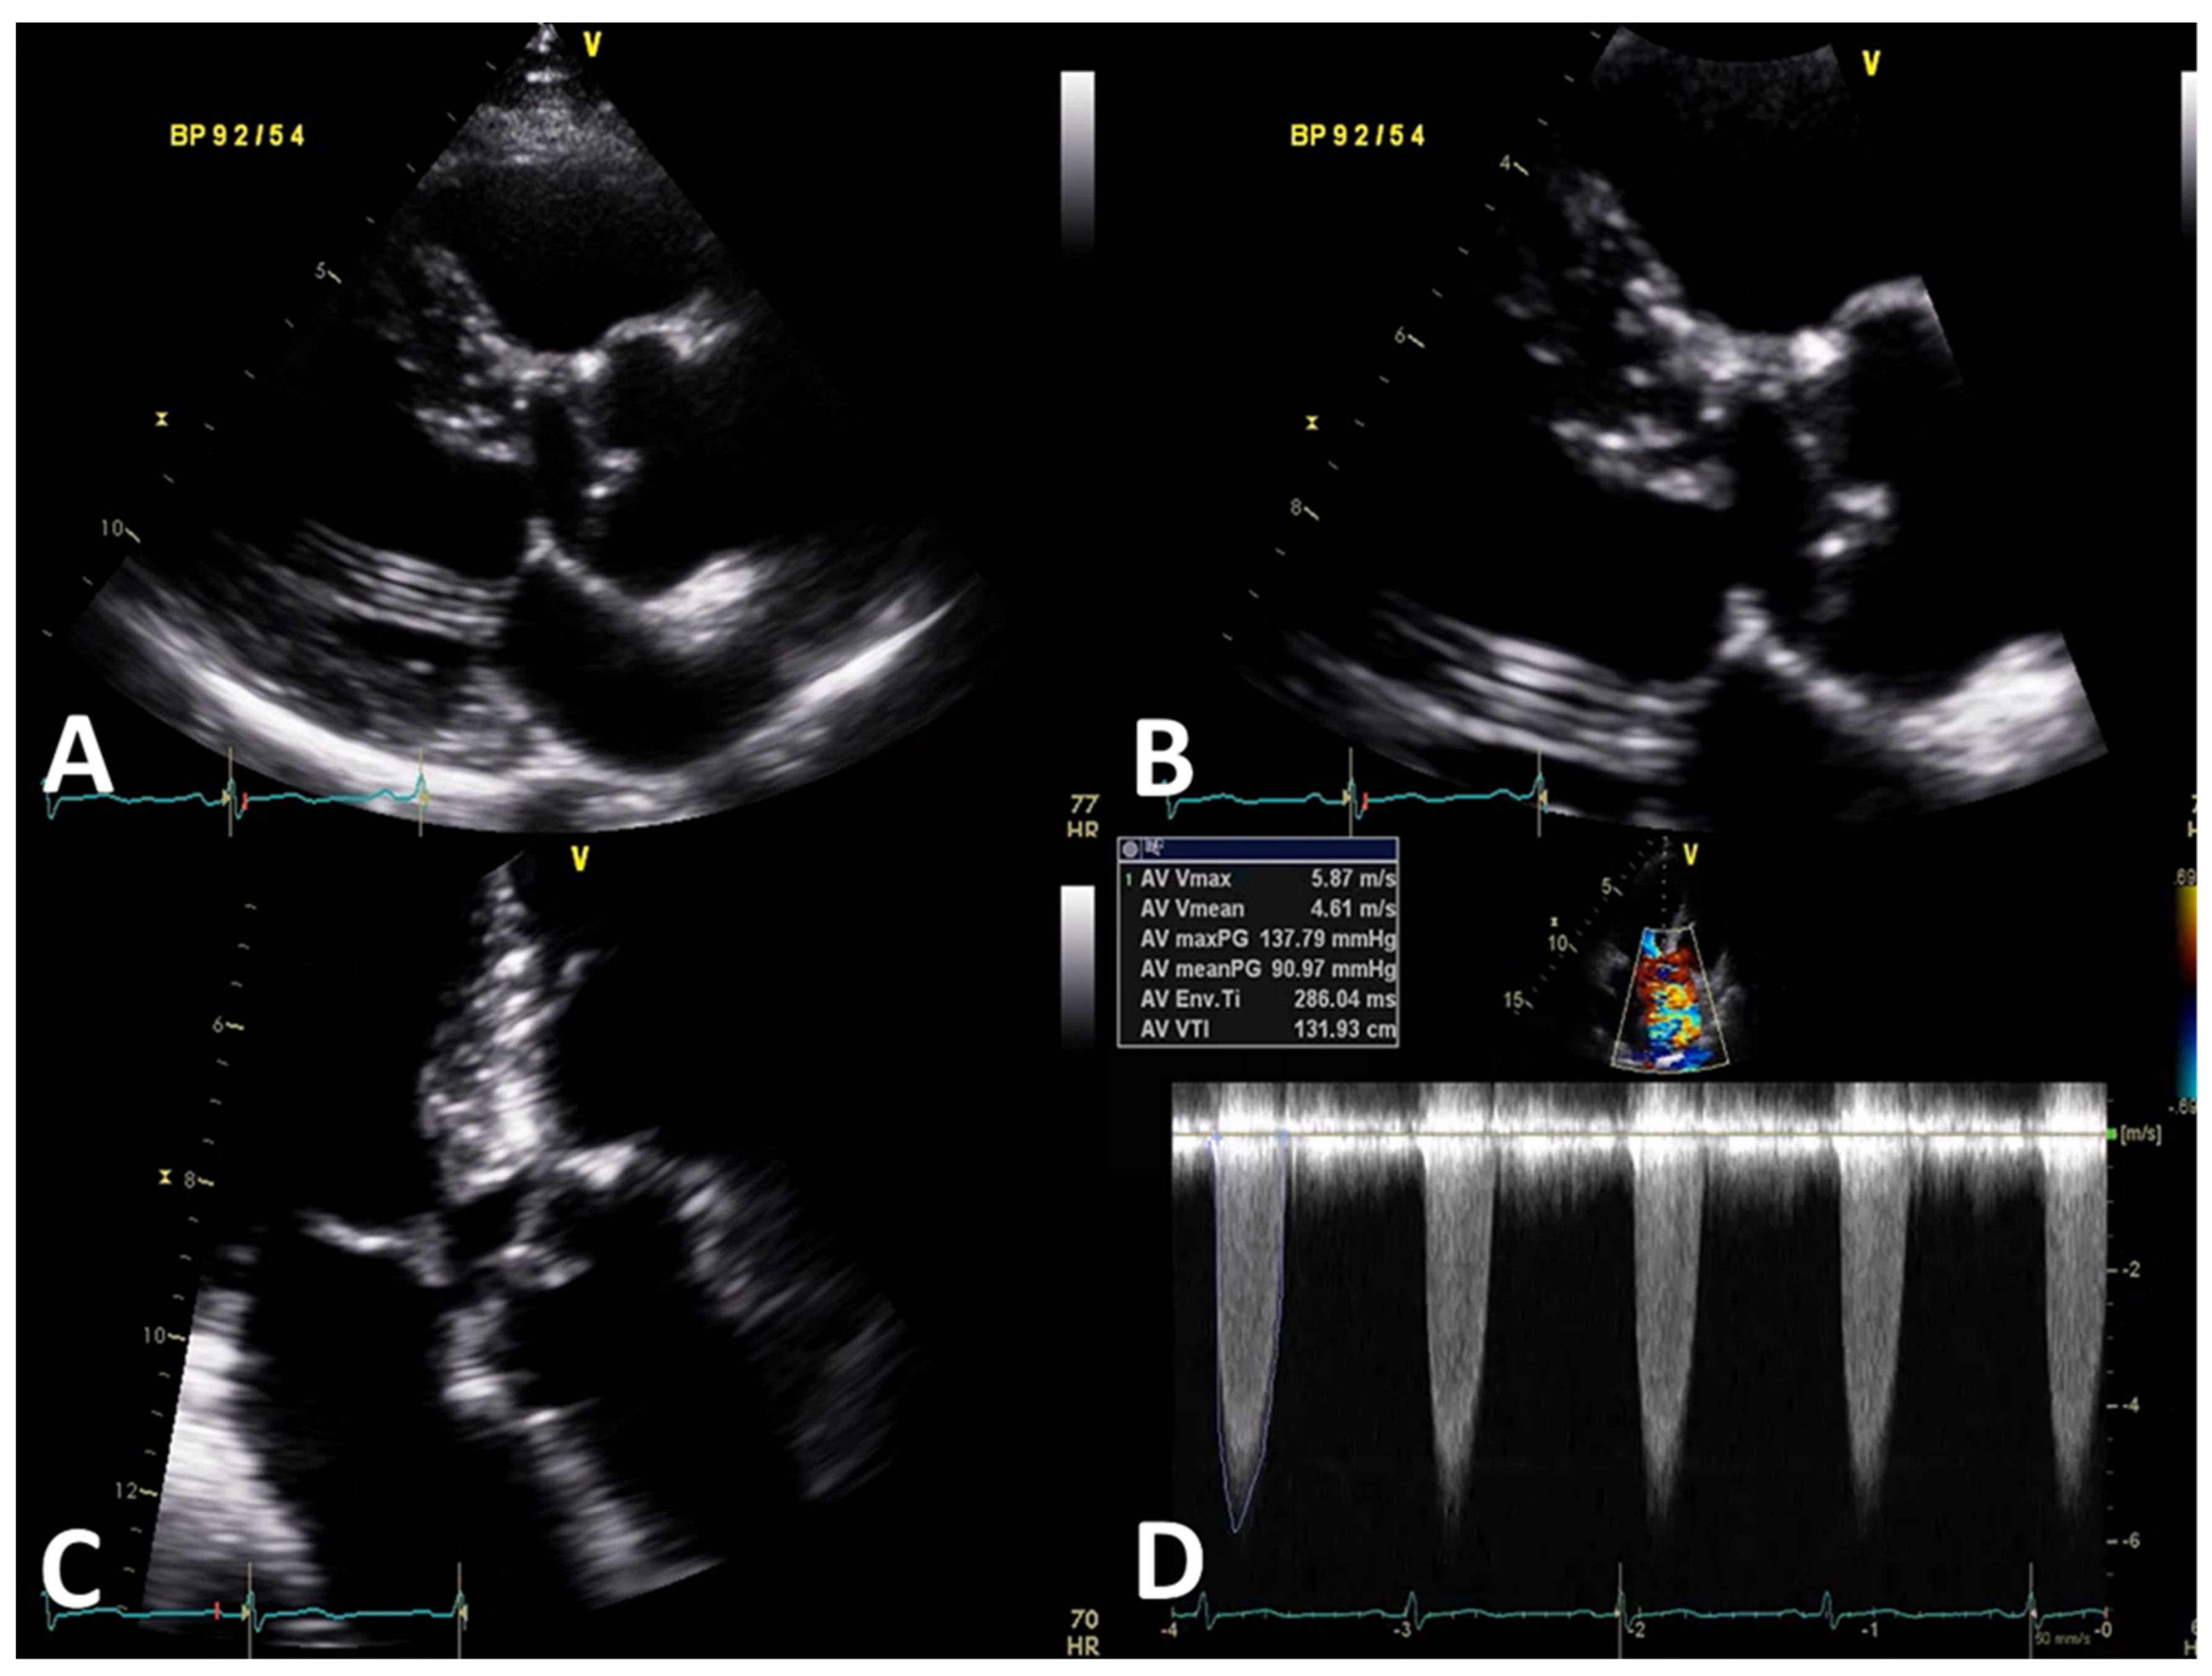

2. Case Presentation